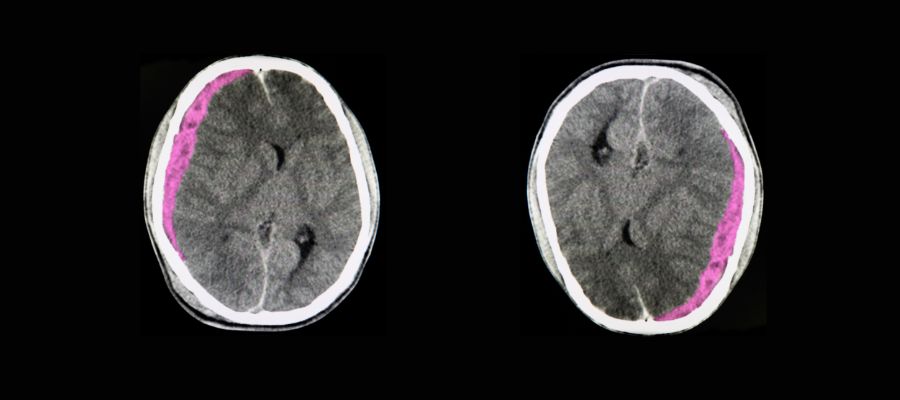

hematome sous dural

Les lésions cérébrales évoluent de manière progressive. Contrairement aux blessures externes immédiatement visibles, les traumatismes internes peuvent mettre plusieurs heures à se manifester. Un hématome sous-dural, par exemple, peut se développer lentement et ne provoquer des symptômes qu'après 6 à 12 heures. Cette évolution insidieuse explique pourquoi une personne peut sembler aller bien immédiatement après le choc, puis présenter des complications sérieuses dans les heures qui suivent.

L'hématome sous-dural représente la complication la plus fréquente et la plus redoutable chez les seniors. Cette accumulation de sang entre le cerveau et la dure-mère peut se développer lentement, sur plusieurs jours ou semaines. Chez les personnes âgées, même un choc mineur peut provoquer cette lésion en raison de la fragilité accrue des vaisseaux sanguins et de l'atrophie cérébrale naturelle qui crée un espace plus important dans la boîte crânienne. Les symptômes peuvent inclure des maux de tête persistants, une somnolence progressive, des troubles de la mémoire ou des changements de comportement.